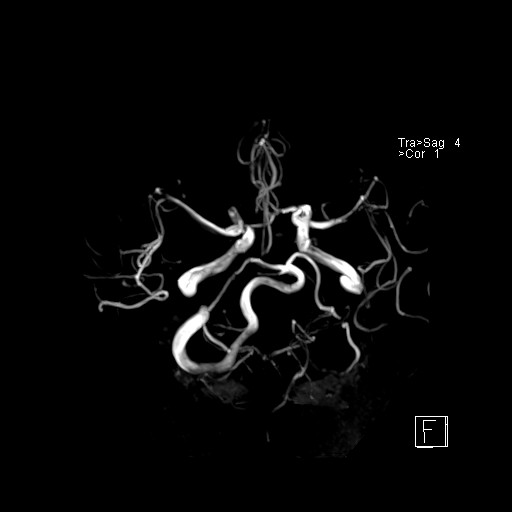

239716 - VILLANUEVA, WILLIAM A. - Number 3 |

|

239716 - VILLANUEVA, WILLIAM A. - Number 3 |